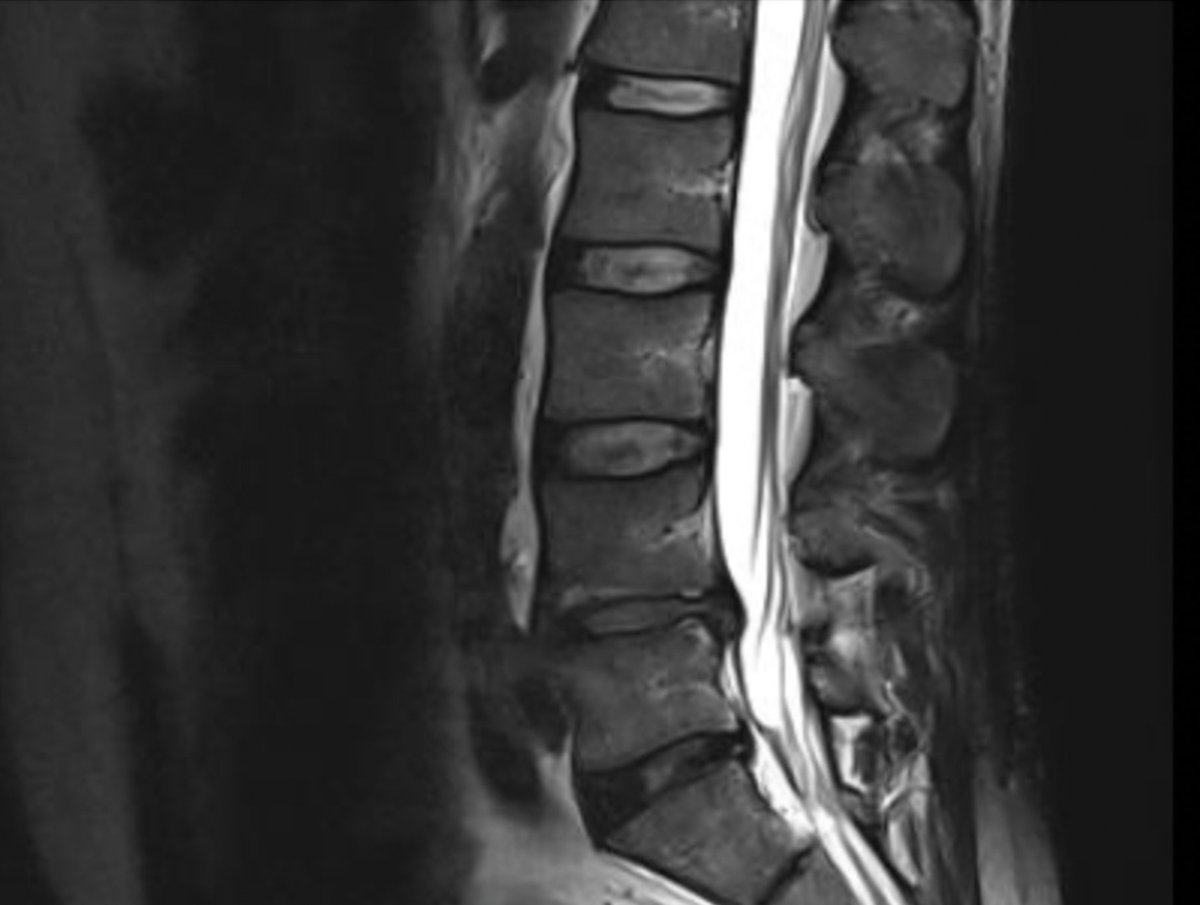

These days I'd rather upload my last 4 back MRI scans and analysis to Reddit and have people there comment on what to do.pic.twitter.com/7wNz2FCzLb